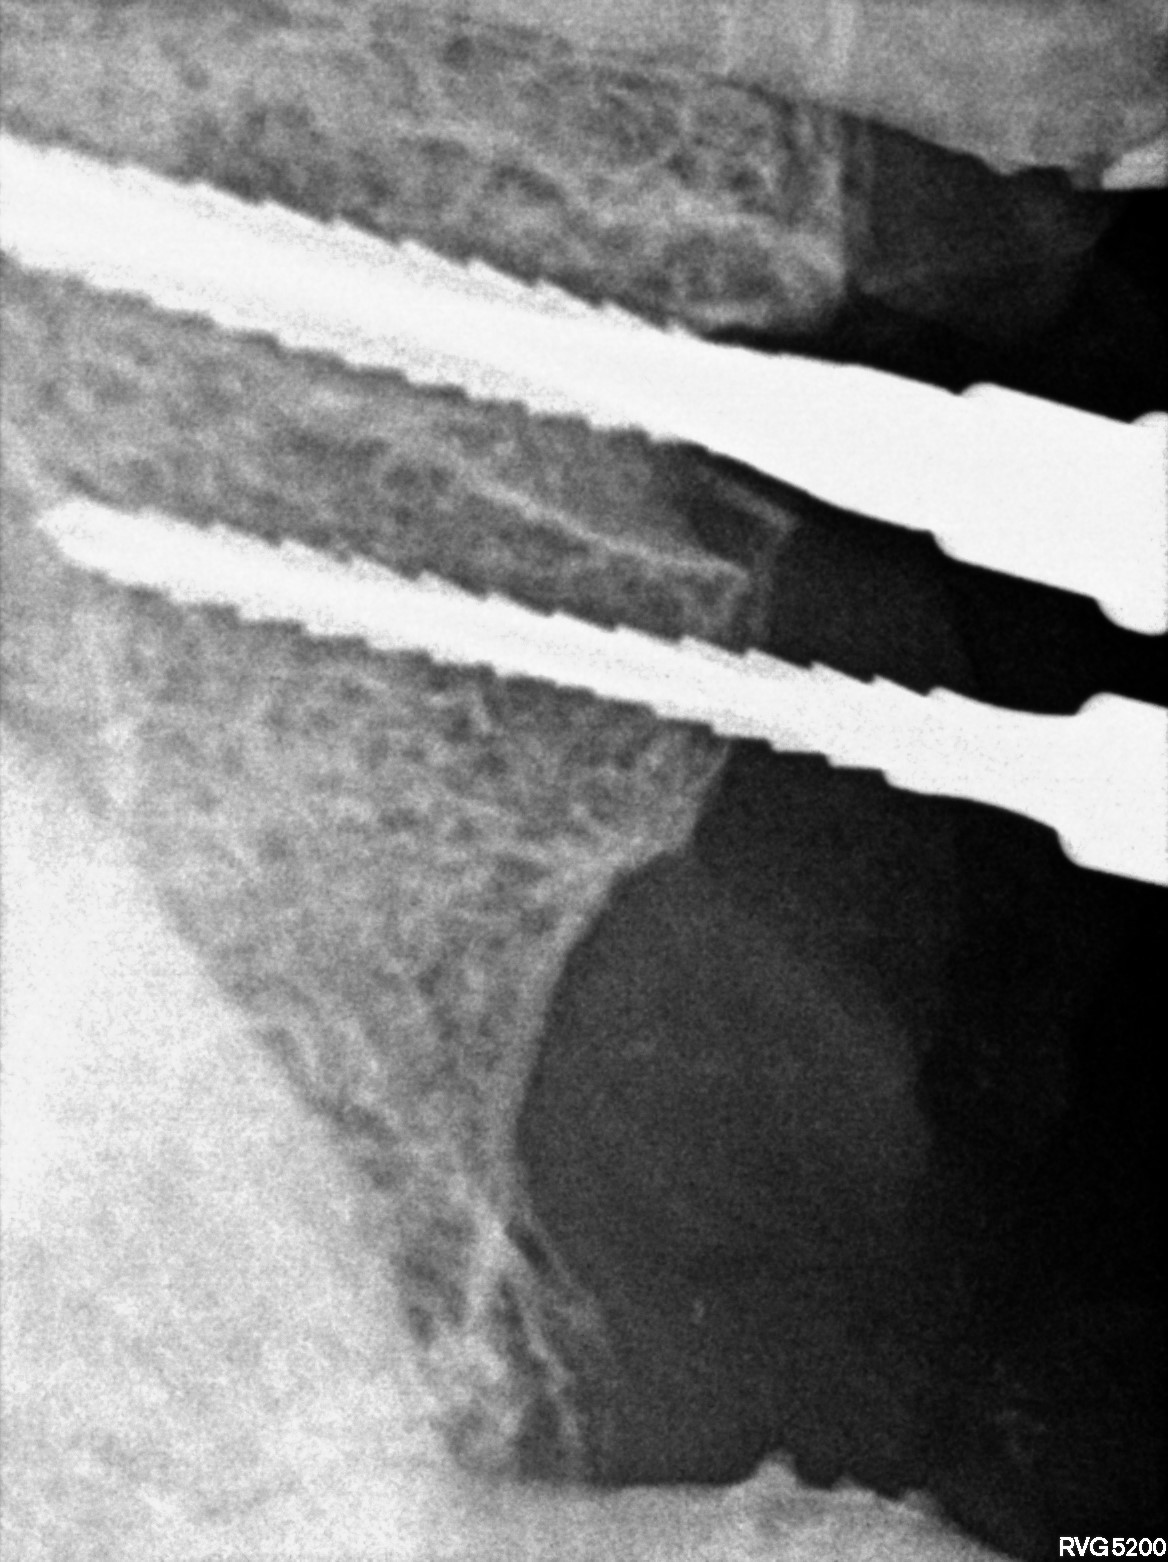

Dental Radiographs FHIR: DocumentReference · LOINC 24641-7

R73.jpg

24641-7